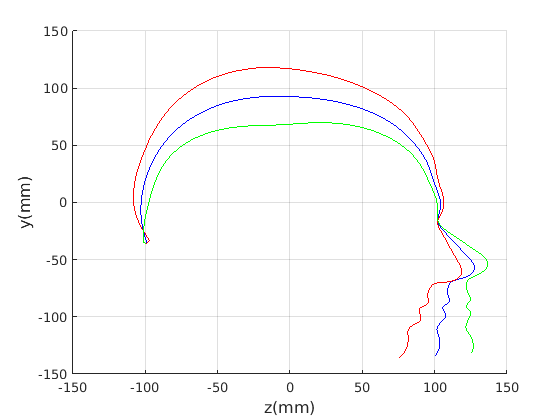

8 A case study of cranial profile model use for intervention outcome evaluation

In this section we take a sample of 25 boys, who are craniofacial craniosynostosis patients, 14 of which have undergone one type of corrective procedure (BS) and the other 11, another corrective procedure (TCR). Providing that the heads are sufficiently symmetrical and are amenable to ellipse fitting, we can parameterise all of these patients’ heads using our scale-normalised craniofacial profile model (2D model with face cropped out). We can then plot their pre-operative and post-operative parametrisations and compare them with the parameterisations of the 100 training examples. The expected result is that the parameterisations should show the head shapes moving nearer to the mean of the training examples. It also reveals which of the dominant modes of shape variation are most affected. The results are shown in figures 31 and 32.

For the BS patient set, the Mahalanobis distance of the mean pre-op parameters (red triangle in Fig. 31) is 4.670, and for the mean post-op parameters (blue triangle) is 2.302. For shape parameter 2 only these figures are 4.400 and 2.156.

For the TCR patient set, the Mahalanobis distance of the mean pre-op parameters (red triangle in Fig. 32) is 4.647, and for the mean post-op parameters (blue triangle) is 2.439. For shape parameter 2 only these figures are 4.354 and 2.439. We note that most of this change occurs in parameter 2, which corresponds to moving height in the cranium from the frontal part of the profile to the rear. In these figures we excluded one patient, who preoperatively already had a near-mean head shape (see red cross near to the origin in Fig. 32, so any operation is unlikely to improve on this (but intervention is required in order to relieve potentially damaging inter-cranial pressure).

It is not possible to make definitive statements relating to one method of intervention compared to another with these relatively small numbers of patients. However, the cranial profile model does show that both procedures on average, lead to a movement of head shape towards the mean of the training population. An example of analysis of intervention outcome for a BS patient is given in Fig. 33 and a TCR patient is given in Fig. 34. The particular example used is highlighted with circles on figures 31 and 32 to indicate pre-op and post-op parametrisations. To our knowledge this is the first use of statistical 3D craniofacial shape models in a clinical study.